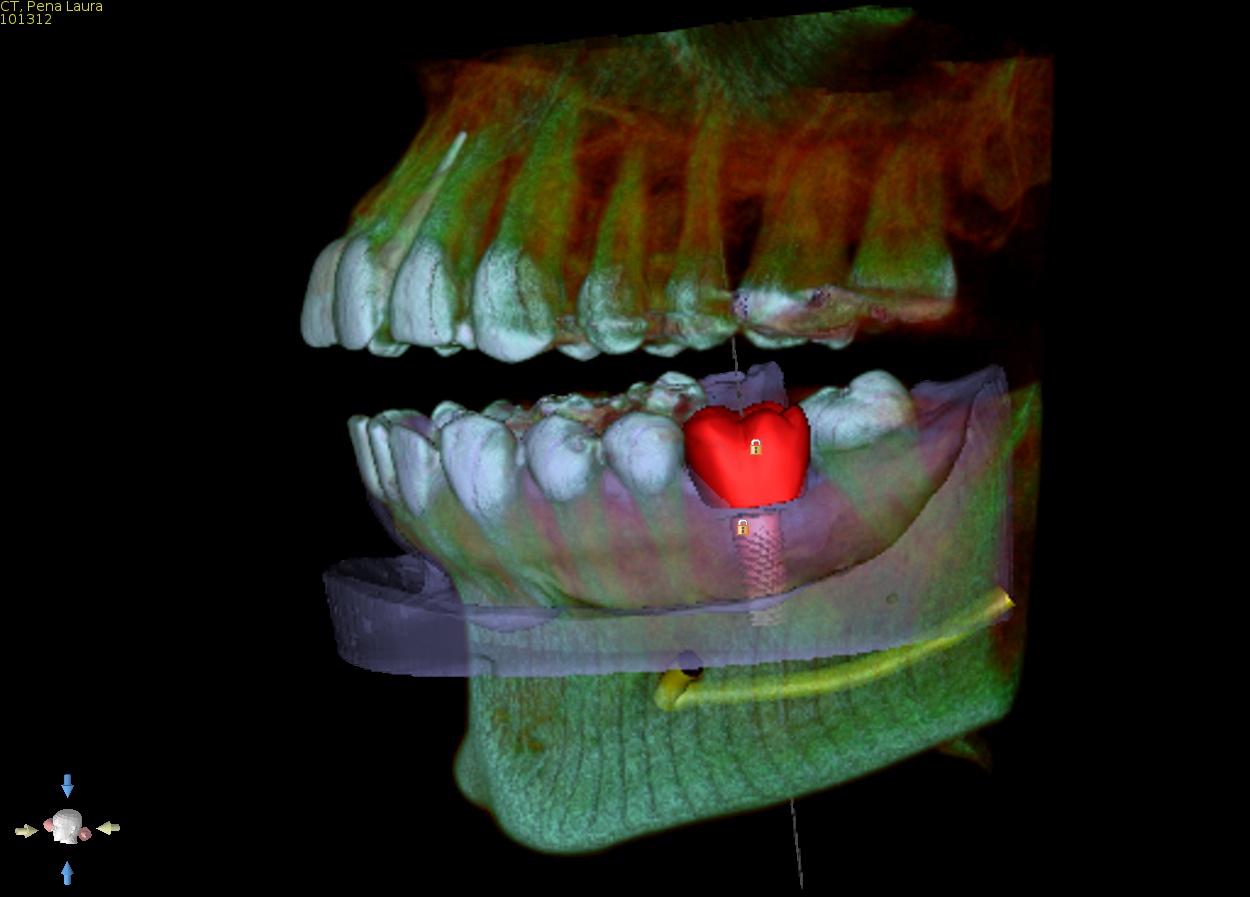

1. CBCT and model merge

Supply a CBCT of the patient and a PVS impression or intra oral scan. We will accurately merge the model with the CBCT so the guide can be made to fit accurately and be tooth and if need be tissue supported. This is a special feature that allows us to offer perfectly fitting guides. Edentulous solutions are also available including tissue or bone supported guides.

2. Virtual implant placement

Supply us with the implant brand and size and we will position it exactly to your specifications and in relation to the virtual final tooth position. We will send a written report for you to check and note any changes if needed. We will not make the guide until you are 100% satisfied with the virtual placement. Alternatively use free software to plan the case yourself and send us the plan file and we can make the guide from that.

Anatomy of an Implaguide